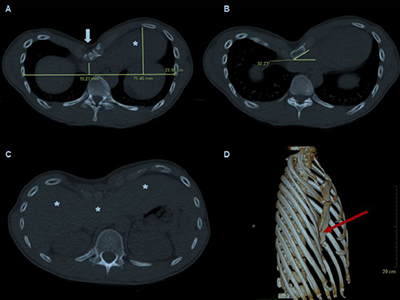

Introducción Las complicaciones del procedimiento de Nuss son bien conocidas. Sin embargo, las publicaciones sobre las complicaciones intraoperatorias y postoperatorias del procedimiento de extracción de barras (BRP) son escasas. ¿Son infrecuentes, desconocidos o no se informan correctamente? ¿Estamos listos para enfrentarlos?